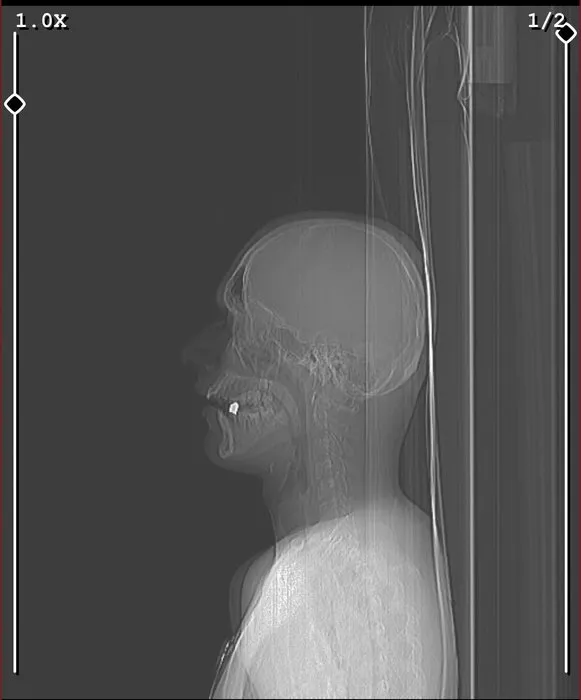

Boynundan giren mermi ağzında kaldı

Eve döndüğü sırada ise aracıyla seyir halindeyken havaya ateş açarak ilerleyen kimliği belirsiz bir magandanın kurşununun hedefi oldu. Kurşun Yazar'ın ensesinden girerek ağzında kaldı.